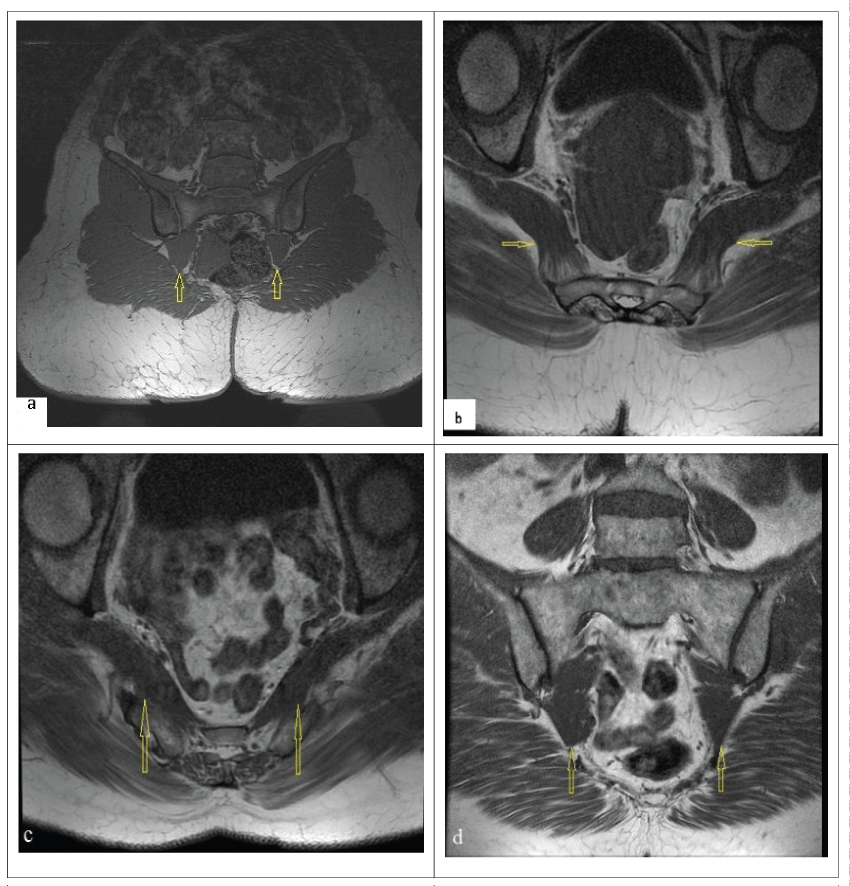

Figure 1: Imaging findings. a) Coronal T1 Pelvic MRI right piriformis muscle hypertrophy (case 1); b) Normal pelvic MRI (case 2); c) Axial T1 pelvic MRI, piriformis muscle hypertrophy/irregularity (case 3); d) Coronal T1 pelvis MRI (case 3); Yellow arrows: piriformis muscle. View Figure 1

36-year old female patient admitted to the pain clinic because of pain moving from hip to right leg for 2 years. She had PTR program 2 times before but she couldn't benefit. Six months before she admitted to the pain clinic, intradiscal procedure (radiofrequency thermo coagulation) had been administered to her by neurosurgery for L4-L5 disc range but reduction in pain hadn't been observed. Pain complaint of the patient, who was taking pregabalin 150 mg 2x1 for two months with neuropathic pain diagnosis, was still ongoing. There weren't any feature in the history of the patient and she wasn't describing a trauma for her hip area. In her examination, her Visual Analog Scale (VAS) score was 6. In physical examination lumbar ROMs range was painful at the end. Paravertebral spasm was present. Right leg Straight Leg Raising (SLR) test was positive in 60°. Her hip ROMs' were clear but range-end was painful. There was sciatic nerve walleix sensitivity at right. Freiberg Test, FADIR Test and Pace Test were positive. Her neurological examination was normal. Lumbar MRI as imaging method of the patient: there was bulging which doesn't create L4-L5 nerve root compression. Right piriformis muscle hypertrophy was detected in the pelvic MRI (Figure 1).

65-year old female patient admitted to our clinic because low back pain and left leg pain for 10 years. She had PTR program 7 months ago but she couldn't benefit. Then she had intradiscal procedure (radiofrequency thermo coagulation) by neurosurgery for L4-L5 disc range but reduction in pain hadn't been observed. There wasn't left hip trauma in the history of the patient. In her examination, her VAS score was 8. There was sensitivity at left gluteal region with palpation. Lumbar extension and flexion were clear but painful at the end of the range. There was L4-L5 paravertebral spasms. Left Straight Leg Raising (SLR) test was positive in 70°. Freiberg Test, FADIR Test and Pace Test were positive. Lumbar MRI as imaging method of the patient: protrusion and facet joint hypertrophy which don't create nerve root compression at L4-L5 and L5-S1 level. Pelvic MRI was normal (Figure 1).

54-year old female patient admitted to our clinic because of pain moving from right hip to down for 1, 5 years. She had PTR program 2 times with LDH diagnosis but she couldn't benefit. Three months before she admitted to the pain clinic, surgical intervention (laminectomy micro discectomy) had been administered to her by neurosurgery for L5-S1 disc range but reduction in pain hadn't been observed. There wasn't hip trauma in the history of the patient. In her examination, her VAS score was 8. All lumbar ROMs' were limited at the end of the range. There were paravertebral spasms. Right Straight Leg Raising (SLR) test was positive in 400. There was sensitivity at right gluteal region with palpation. Freiberg Test, FADIR Test and Pace Test were positive. Lumbar MRI of the patient: there was bulging which doesn't create L4-L5 nerve root compression and laminectomy defect and soft tissue increment, facet joint hypertrophy at L5-S1 were detected. In pelvic MRI, piriformis muscle hypertrophy and irregularity were detected (Figure 1).

In all 3 patients, Freiberg, FADIR and Pace Tests were positive. Lumbar and pelvic MRI was used as imaging method. In each 3 cases, there were bulging not forming nerve compression and protrusions in lumbar MRI. In pelvic MRI, there was hypertrophic piriformis muscle disorder in case 2 and there was disorder in piriformis muscle in cases 1 and 3.